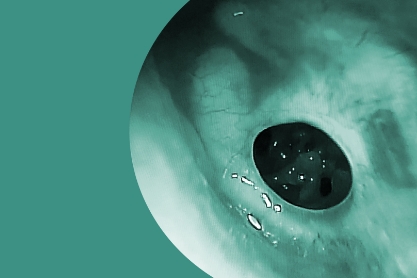

Patologías

Existen numerosos factores patológicos que pueden provocar la sordera o pérdida de la audición. Conocé algunos de ellos y trabajemos juntos para tratarlo.

Prácticas

El oído es un órgano del cuerpo humano donde muchas funciones complejas y delicadas se combinan. Es por eso, que la realización de distintos procedimientos y técnicas son necesarias.